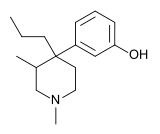

4-Phenylpiperidines

Pethidines (meperidines)

Others